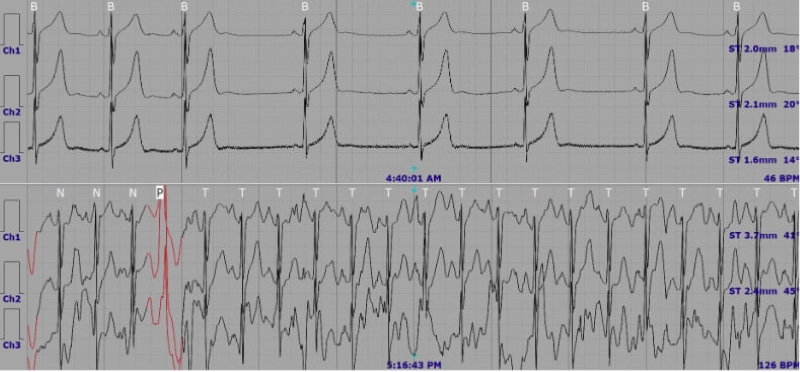

Sau khi thăm khám, bác sĩ đã chỉ định thực hiện các xét nghiệm và kỹ thuật cận lâm sàng cần thiết nhằm đánh giá toàn diện chức năng tim mạch. Kết quả siêu âm tim ghi nhận tình trạng hở van hai lá mức độ nhẹ. Đặc biệt, kết quả Holter điện tim 24 giờ cho thấy nhiều bất thường có ý nghĩa lâm sàng, bao gồm:

- Ngoại tâm thu thất số lượng rất nhiều (23.686 nhịp), chiếm 22,6% tổng số nhịp tim;

- Ngoại tâm thu thất đa ổ, có xuất hiện nhịp đôi, nhịp ba (phân độ Lown 4A);

- Nhịp tim chậm kéo dài (hơn 6 giờ với tần số < 60 nhịp/phút);

- Khoảng QTc trung bình kéo dài (470 ms).

Bất thường được phát hiện trên kết quả Holter điện tim 24 giờ

Dựa trên tổng hợp kết quả lâm sàng và cận lâm sàng, bệnh nhân được chẩn đoán xác định ngoại tâm thu thất số lượng nhiều (chiếm 22,6% tổng số nhịp tim), phân độ Lown 4A. Trước tình trạng này, bác sĩ đã chỉ định điều trị nội khoa, đồng thời tư vấn theo dõi sát các triệu chứng, điều chỉnh lối sống phù hợp và hẹn tái khám định kỳ nhằm đánh giá đáp ứng điều trị cũng như kiểm soát nguy cơ tiến triển của rối loạn nhịp tim.